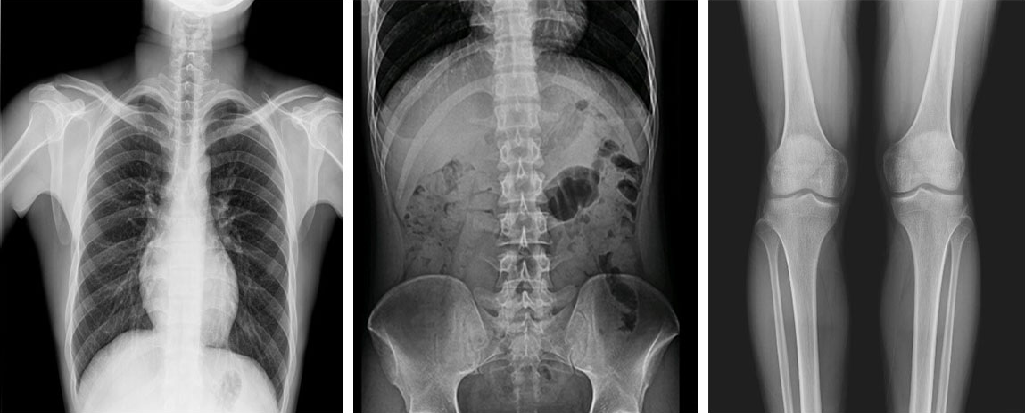

在功能上,動態(tài)DR已不再局限于簡單的拍片功能,而是集數(shù)字化攝影、數(shù)字化透視、數(shù)字化造影、數(shù)字化實時點片于一體,臨床用途廣泛,可應(yīng)用于臨床各科室,如體檢科、內(nèi)科、外科、骨科、創(chuàng)傷科、急診科等。

與此同時,動態(tài)DR的成像視野與精度也勝于靜態(tài)DR。動態(tài) DR17×17 英寸方形幅面進行動態(tài)成像,能夠?qū)鹘y(tǒng)動態(tài)造影幅面小的問題全部解決,同時由于幅面較大,臨床操作技師能夠在一個大的幅面下觀察診斷,當看到病變部位時實時高清點片,從而很好地捕捉到病變點,也大大降低了檢查時間。

PLD8000系列數(shù)字透視攝影系統(tǒng)集數(shù)字化攝影、數(shù)字化透視、數(shù)字化造影、可視化點片等多種功能于一體,搭載高品質(zhì)高壓發(fā)生器、球管與平板探測器,確保性能穩(wěn)定的同時成就高清成像,同時提高機架自動化程度,并且配備智能化電動床體,帶來智能化、人性化操作體驗,全面滿足各級醫(yī)療機構(gòu)放射檢查需求。